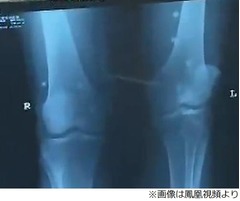

紹介された医師は鄒さんの症状を聞くと、背中や臀部、ひざなどに合計42粒の真珠を埋め込んだ。ここですぐに鄒さんの身体に異変が生じていれば、結果的に大事には至らなかったのかもしれない。しかし、手術当初は症状がきちんと緩和されていたそうで、昨年になって脚に痛みが出るようになり、やっと「騙された」と思うようになったという。

鄒さんの診察を担当した長沙年輪整骨科病院の医師は「真珠を埋め込んだことと直接の関係はないが、彼は病状を長く引っ張りすぎてしまい、治療に最適な時期を逃してしまった。今すぐに真珠を取り除かなければ手術にも大きな悪影響を及ぼしかねない」と話している。実際、鄒さんの大腿骨頭は壊死していたという。